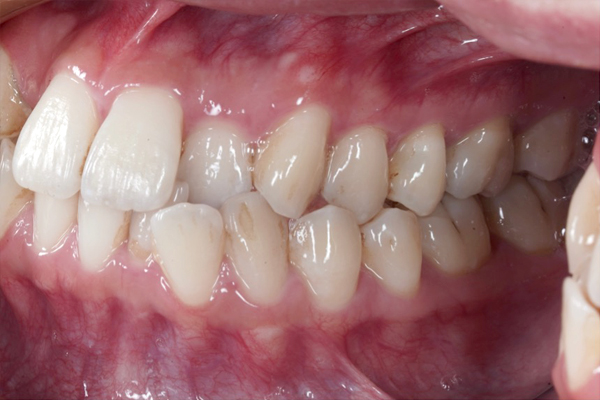

BEFORE

• ずっと叢生(ガタガタ)が気になっていた。

• 患者様は抜歯をしたくない。

• ワイヤー矯正でスペースを作り、非抜歯(抜歯をしないで)並べていく治療方針を計画しました。